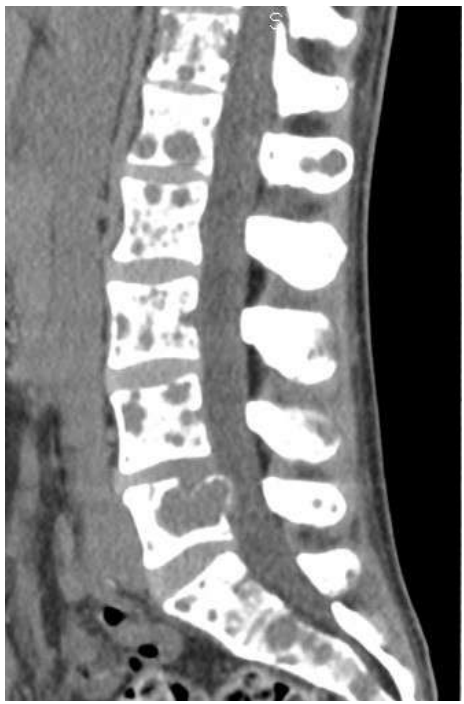

Um paciente de 65 anos de idade, internado para investigação de dor lombar, evoluiu com rebaixamento no nível de consciência e apresentou os achados tomográficos mostrados a seguir. Desidratado +++/4, descorado +/4, anictérico e acianótico. SV: PA de 140 x 80 mmHg; FC de 120 bpm; Glasgow 12; TEC de 3 s; pupilas isofotorreagentes; e FR de 22 iprm. Exames relevantes: Hb 7,8; leucócitos 8.000; plaquetas 180.000; Cr 1,9; e Ur 130.

Com base nesse caso hipotético, assinale a alternativa que apresenta a conduta mais apropriada.